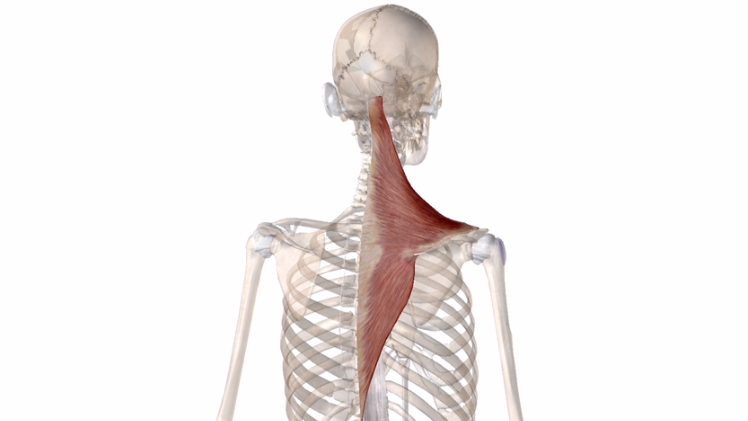

僧帽筋↓